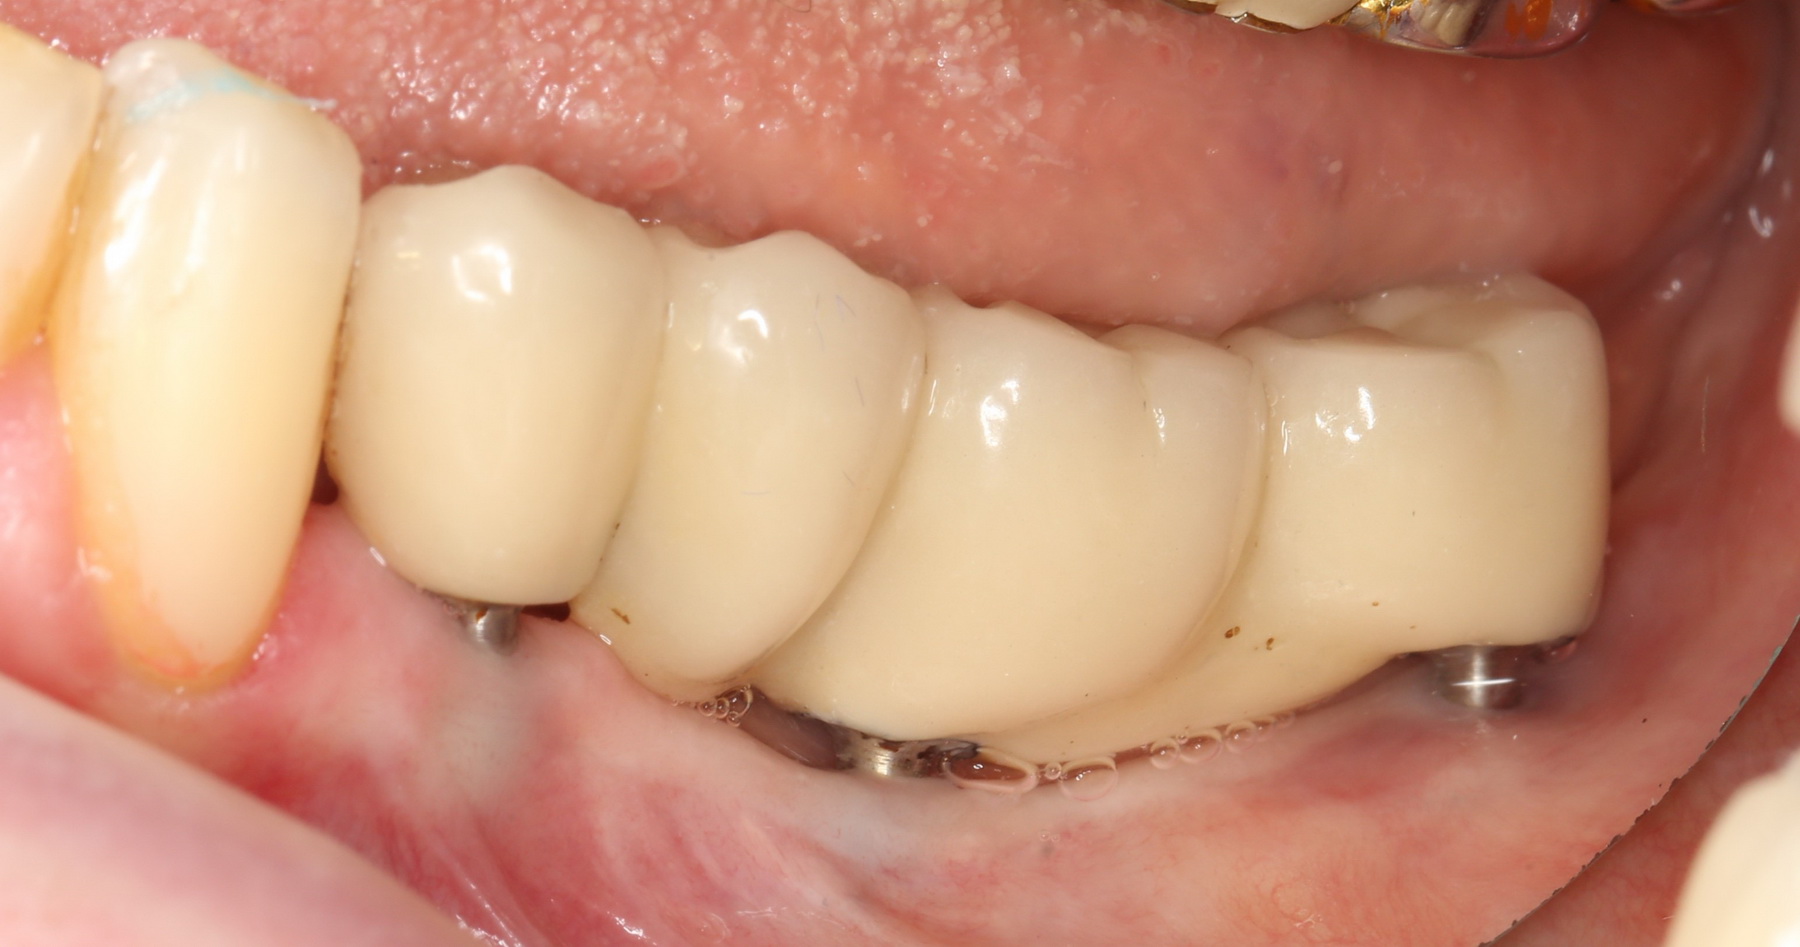

Нижние, вроде как, вполне держатся, на них стоят постоянные металлокерамические коронки. Помните, что я говорил про один из главных критериев качественной имплантологической работы? Состояние десны вокруг имплантов!

Хотите на это посмотреть? Этого не покажут, рекламируя базальную имплантацию:

То есть, друзья, десны нет. За подобную работу в наших клиниках рвут диплом в клочья и выгоняют нафиг. Для базальной имплантации, такая ситуация — норма:

И теперь представьте, как за всем этим ухаживать? Как этим жевать, если учесть тот факт, что ножка импланта, торчащая из десны, легко гнется? И сколько такие импланты вообще прослужат, если учесть сложную гигиену и неудобную форму протеза в этом участке?

Жаль, но мы вынуждены эти базальные импланты удалить, проводить остеопластику и ставить другие, обычные винтовые импланты. И, к счастью, уже закончили эту работу, как нибудь расскажу вам о ней.